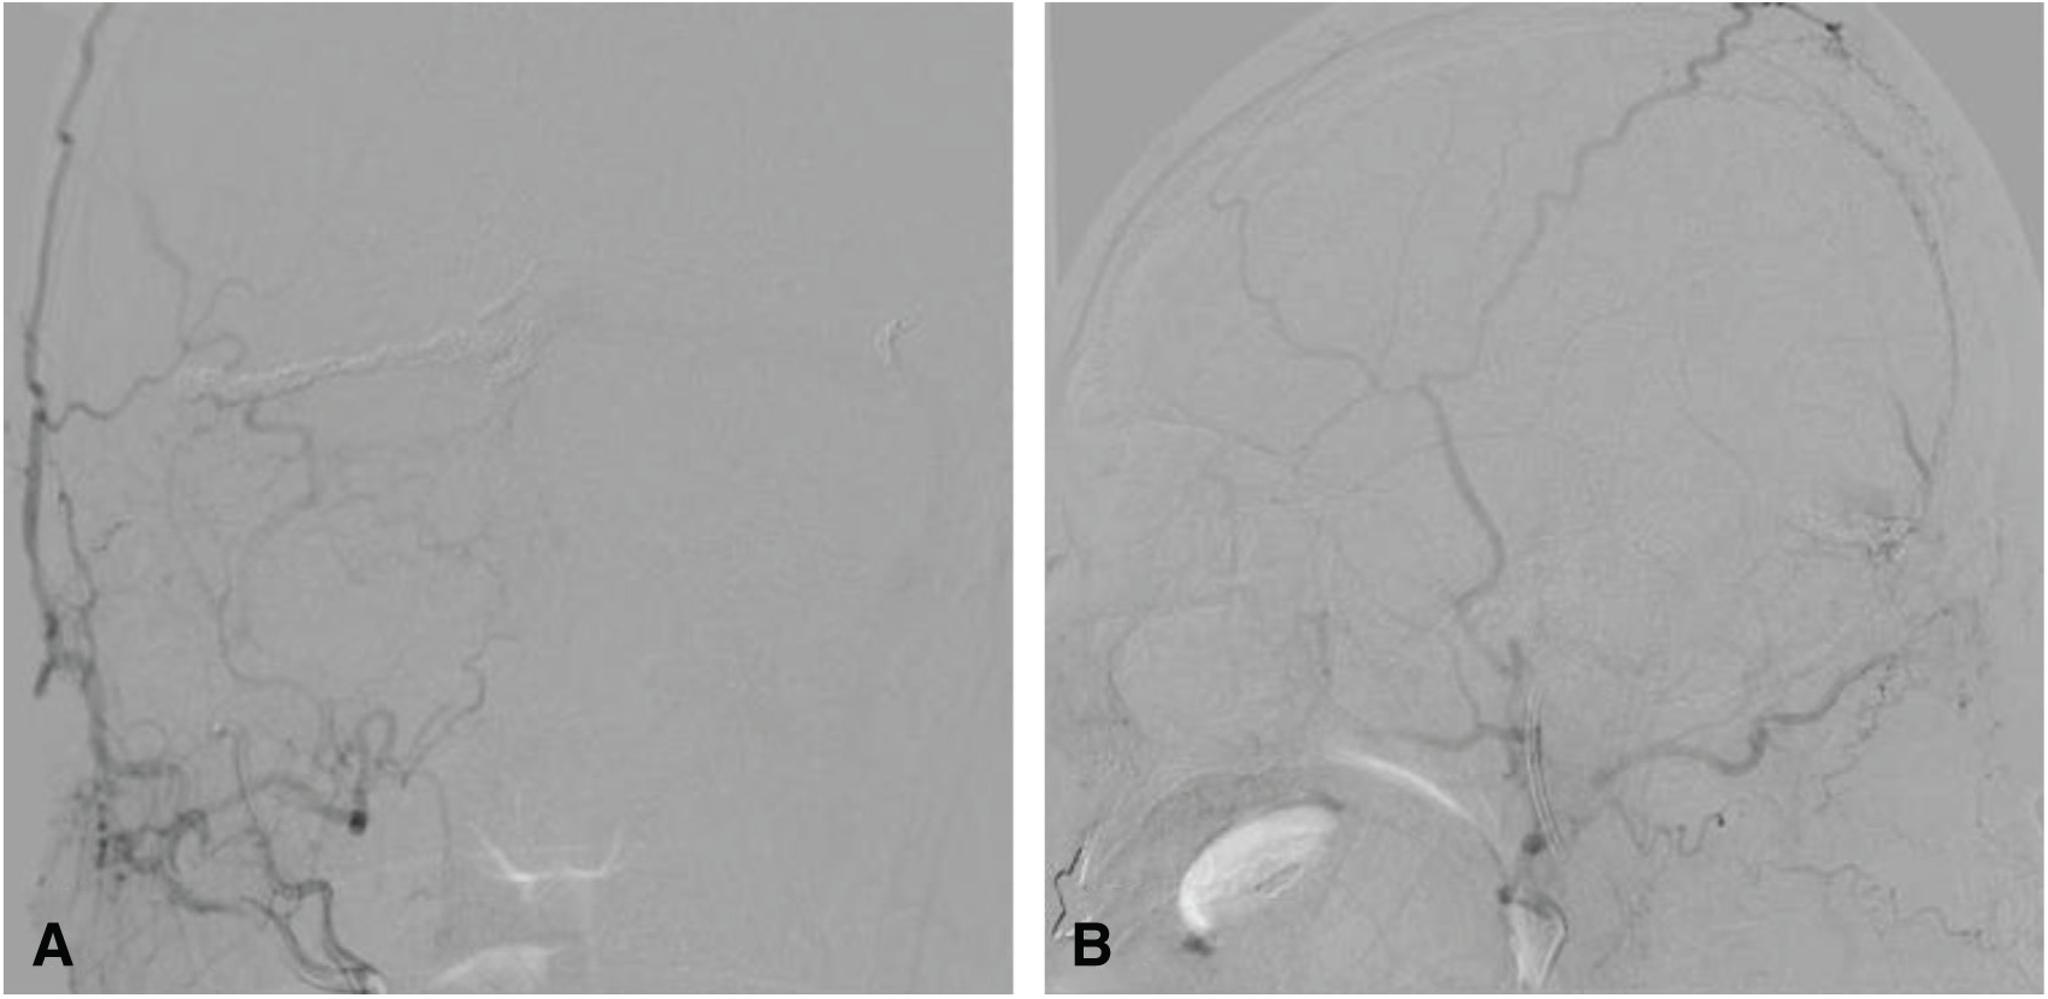

The patient was a 65-year-old man. Cerebral angiography demonstrated an aggressive dAVF involving the TSS, superior sagittal sinus (SSS), and the sinus confluence, with severe cortical and deep venous reflux. We performed multiple transarterial and transvenous embolizations for the TSS and sinus confluence lesion. The shunt disappeared almost completely after embolization. A high signal intensity that had been apparent in the SSS and straight sinus (StS) on ASL imaging before embolization disappeared after embolization. ASL imaging 3 months after embolization revealed slightly a high signal intensity in the StS, which was considered to be due to recurrence of the lesion. Moreover, recurrence of the confluence and TSS-dAVF was observed on cerebral angiography 6 months after embolization. As additional embolization was considered difficult, radiation therapy was recommended, but the patient refused; therefore, follow-up was performed. As ASL imaging findings were consistent with cerebral angiography findings, careful examination and monitoring of changes on ASL imaging were subsequently performed.

患者为一名65岁男性。脑血管造影显示为侵袭性硬脑膜动静脉瘘,累及横窦、上矢状窦(SSS)和窦汇,伴有严重的皮质和深部静脉逆流。我们对横窦和窦汇病变进行了多次经动脉和经静脉栓塞治疗。栓塞后分流几乎完全消失。栓塞前ASL成像中在SSS和直窦(StS)中明显的高信号强度在栓塞后消失。栓塞后3个月的ASL成像显示StS中有轻微的高信号强度,这被认为是由于病变复发所致。此外,栓塞后6个月的脑血管造影显示窦汇和TSS-dAVF复发。由于考虑再次栓塞困难,建议进行放射治疗,但患者拒绝;因此,进行了随访。由于ASL成像结果与脑血管造影结果一致,随后对ASL成像的变化进行了仔细检查和监测。